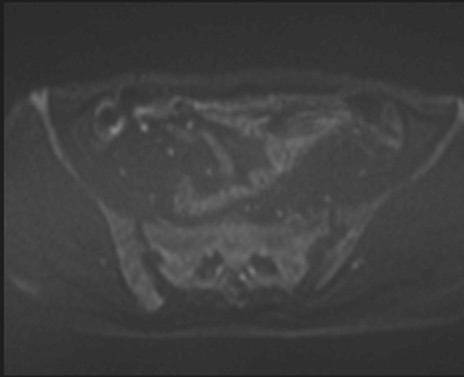

MRI(4日後)